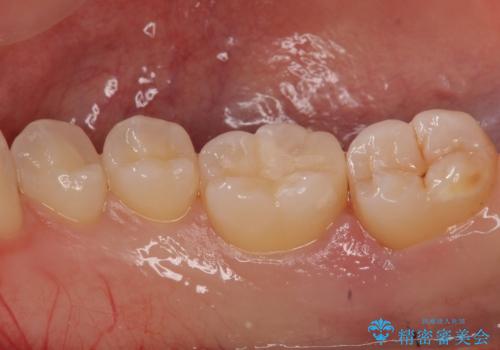

奥歯の虫歯 セラミックインレーによる治療

- 検査をしたところ奥歯に小さな虫歯を発見。

大きくなる前に白い詰め物で治療がしたいとのことでセラミックインレーでの治療になりました。

口の中を見ただけでは異常がないのにレントゲン画像上では虫歯がある、といったことは多々あります。奥歯とはいえ、口をあけると外から見えてしまうため白いセラミックでの治療ができたことを大変喜んでいただけました。